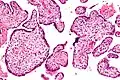

Micrograph of villitis of unknown etiology. H&E stain.

Histomorphologically, VUE is characterized by a lymphocytic infiltrate of the chorionic villi without a demonstrable cause. Plasma cells should be absent; the presence of plasma cells suggests an infective etiology, e.g. CMV infection.